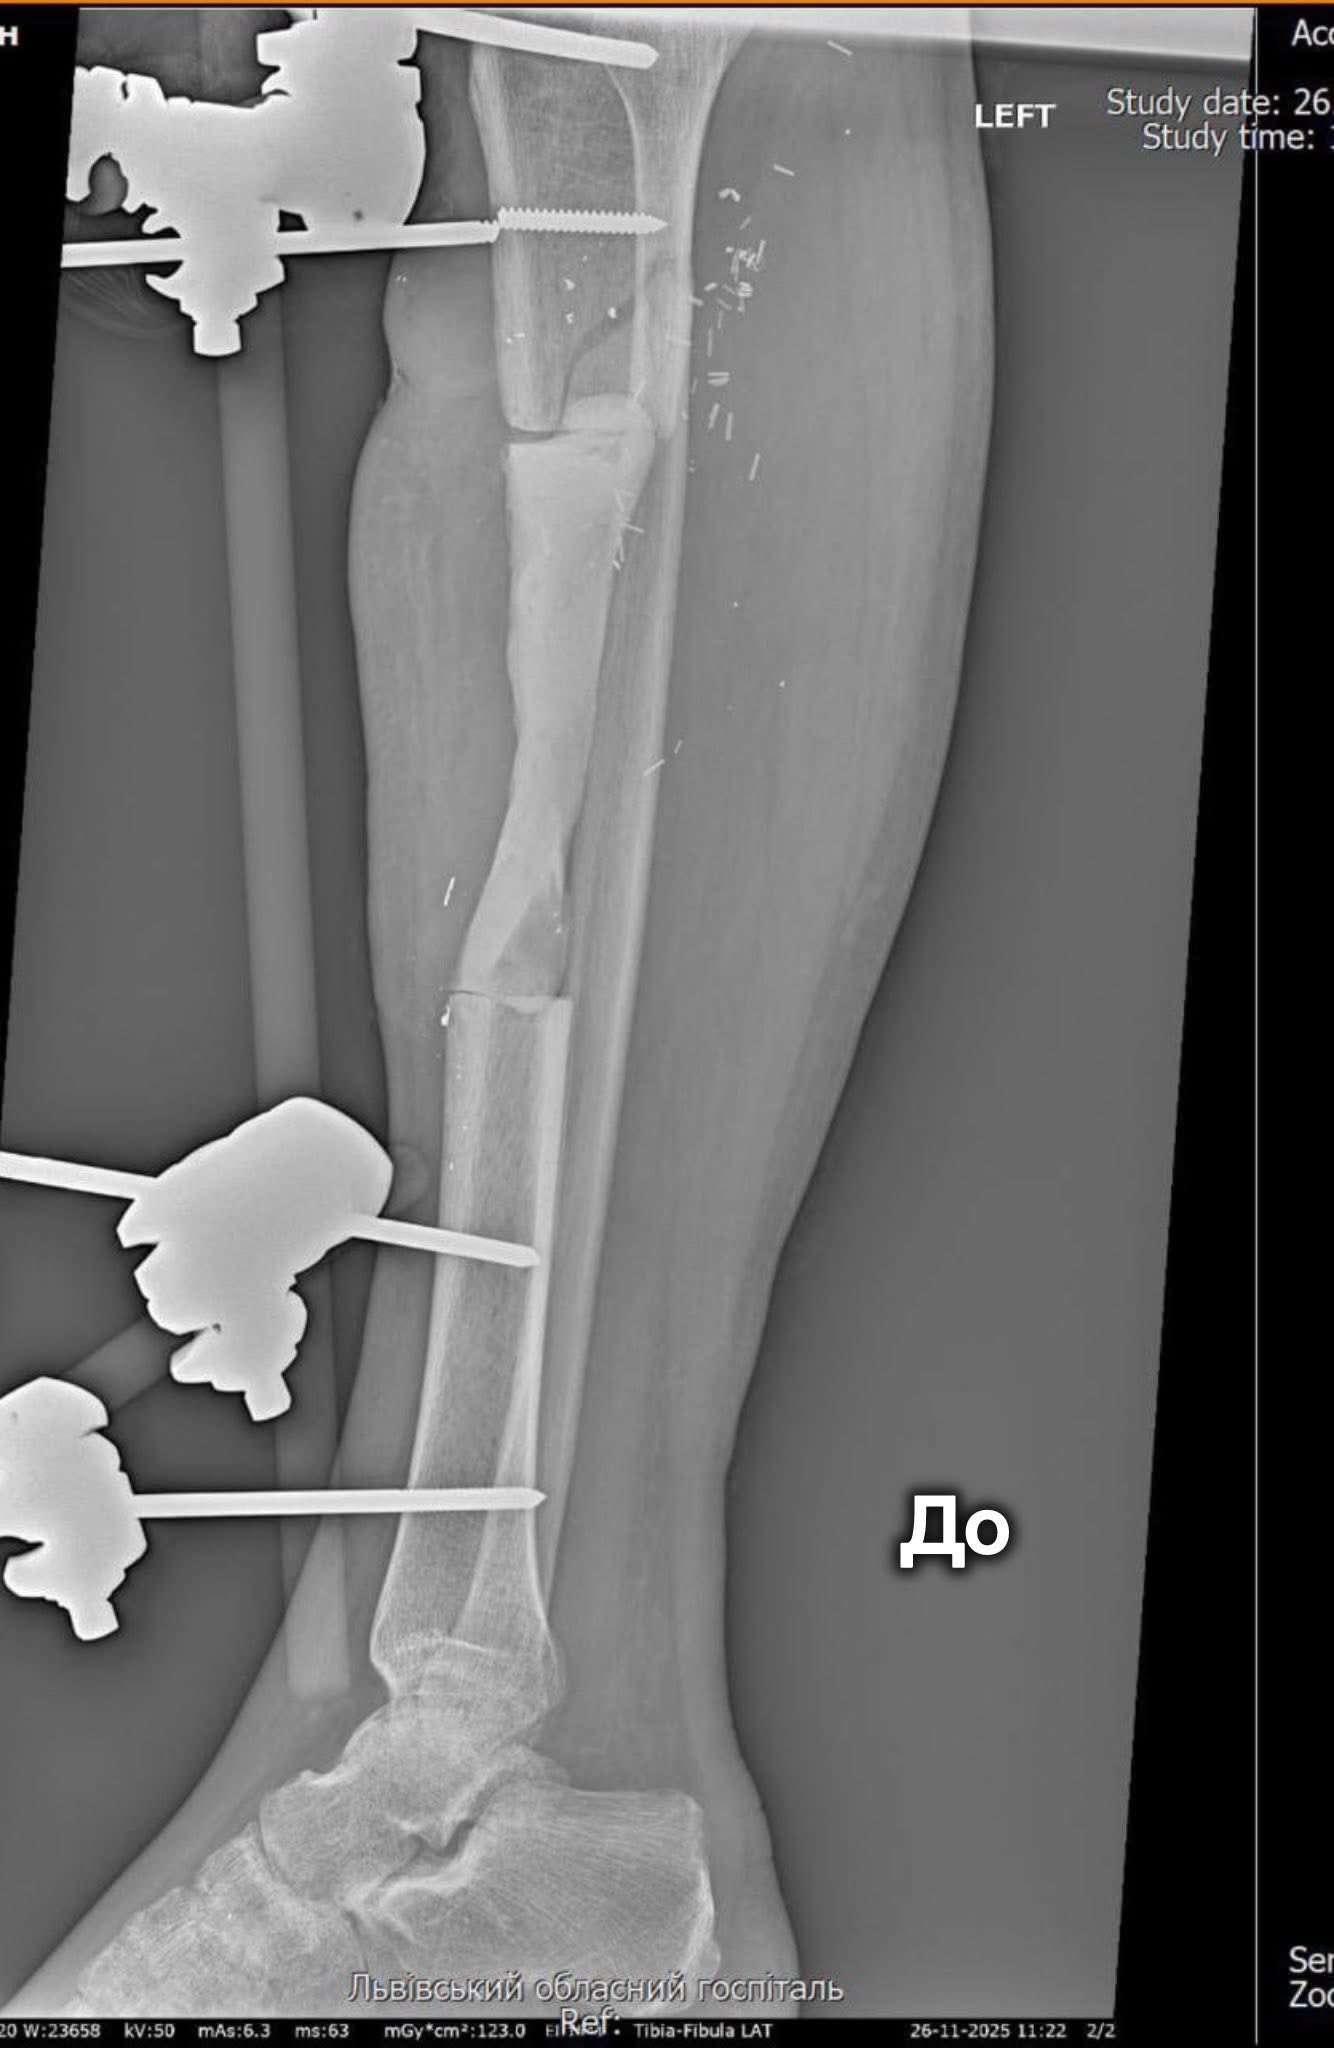

Пацієнтом став військовослужбовець із критичним дефектом кістки — ушкодження сягало 12,5 сантиметра. У таких випадках стандартне лікування часто не дає результатів, тому медики вирішили застосувати методику Маскулет. Вона передбачає два етапи: спершу лікарі формують спеціальну «камеру» для кістки, а згодом заповнюють її кістковою тканиною та стабілізують уламки.

«Техніку Маскулет нерідко називають «операцією останньої надії», адже вона дає шанс на відновлення у випадках важких вогнепальних поранень і значних кісткових втрат. Метод дозволяє уникнути тривалого використання апаратів зовнішньої фіксації та скорочує шлях пацієнта до повноцінного відновлення», — зазначають у госпіталі ветеранів.